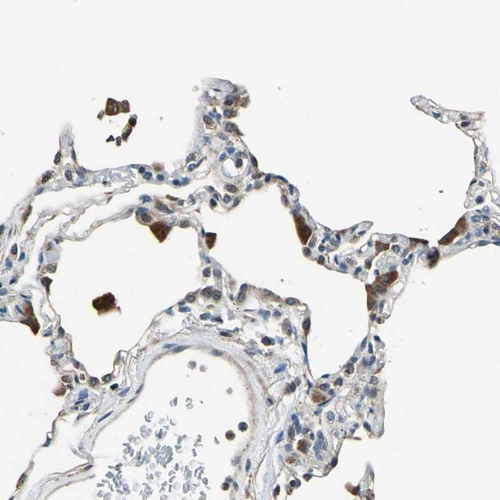

Immunohistochemical staining of human spleen shows moderate cytoplasmic positivity in sinusoids.